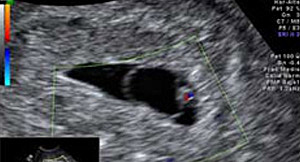

El latido del corazón del bebé se ve muy claro en la ecografía y su tubo neural ya empieza a cerrarse. De ahí la importancia de la suplementación de ácido fólico en el embarazo.El embrión ya mide entre 2 y 4 milímetros en la semana 6 de embarazo. Esta medida es la longitud desde la cabeza (el polo cefálico) hasta el final de la columna vertebral (el polo caudal). Por eso a esta medida se le llama LCC, Los ojos se están formando así como el primer vestigio cerebral

La ecografía puede decirnos muchas cosas: si hay malformaciones graves, si falta alguna extremidad, o incluso adelantar el sexo del bebé, porque ya están formados los genitales externos. La embarazada suele entrar en una etapa de mayor estabilidad (menos náuseas y vómitos) a medida que su útero crece.La cabeza sigue ocupando la mitad de la longitud embrionaria. Aparecen barbilla y cuello a medida que la cabeza se va separando del pecho. Empiezan a diferenciarse las uñas de los dedos.